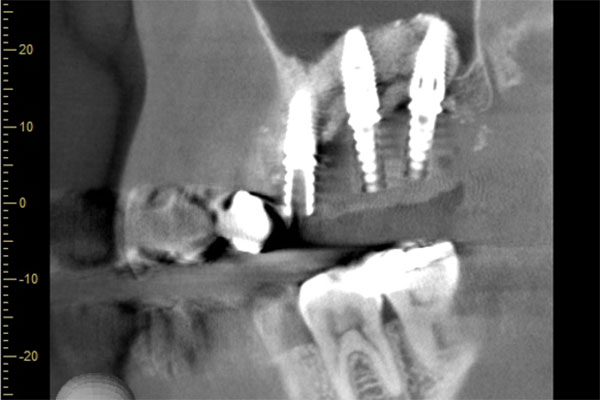

①親知らず手前の歯はクラウン(白い不透過像)直下に大きな透過像(黒い部分)が見られこのような場合は抜歯になる確率が高いです。

②歯根分岐部(中央部)に及ぶ歯周炎ー根尖性歯周炎の原因はクラウン除去後にマイクロスコープ下にて破折線を確認したため抜歯となりました。

コーンビームCT像を確認すると左側上顎の骨は無くインプラント埋入の際は上顎骨に骨造成が必要と思われたため上顎洞挙上術(サイナスリフト)を併用、インプラント埋入を行うプランとしました。

処置前では黒い透過像(骨が無い)があるが骨造成後1年経過、インプラントテック(仮歯)を入れた際では上顎洞内及びインプラント周囲に白い不透過像(骨がある)が確認できます。